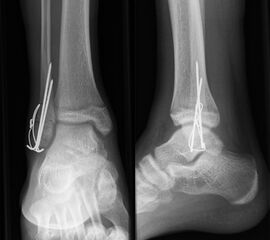

Die häufig nicht dislozierten knöchernen Ausrisse können konservativ behandelt werden. Dislozierte Fragmente sollten operativ mit Kirschner-Drähten oder Schrauben fixiert werden (Abb. 32). Die Nachbehandlung umfasst eine 4-wöchige Entlastung im US-Gips. Eine Röntgenkontrolle erfolgt nach Gipsabnahme. Freies Gehen sollte nach 6 Wochen möglich sein. Danach ist auch eine sportliche Belastung des Sprunggelenks möglich (v. Laer 2013).

Eingebrachtes Osteosynthesematerial sollte vor der Vollbelastung entfernt werden.